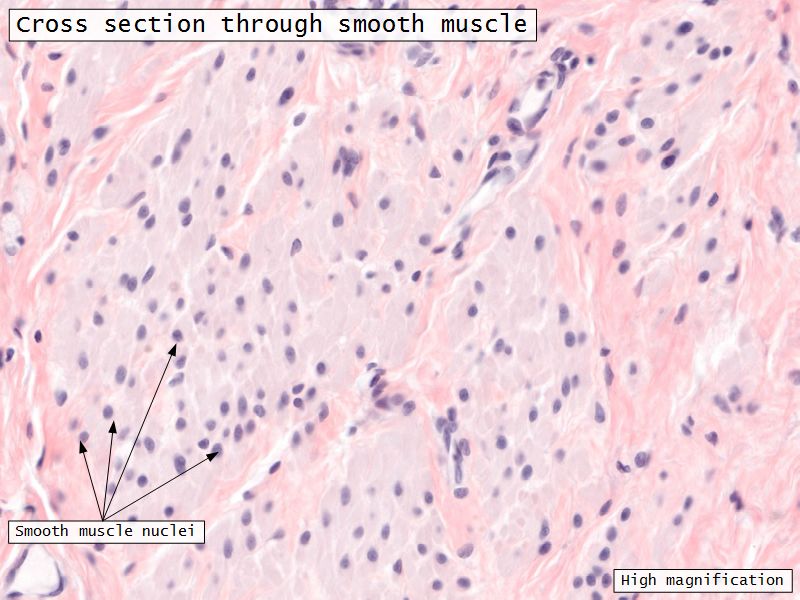

Myometrium

- Enlarge during pregnancy

- Expulsion fetus & placenta

- 3 layers indistinct smooth

- Inner longitudinal/oblique

- Central circular

- Large blood vessels

- Stratum vasculare

- Outer longitudinal/oblique

Muscle layer

- Thin inner circular

- Thick outer longitudinal

- External orifice ring of skeletal muscle

Muscle layer

- Inner circular

- Outer longitudinal